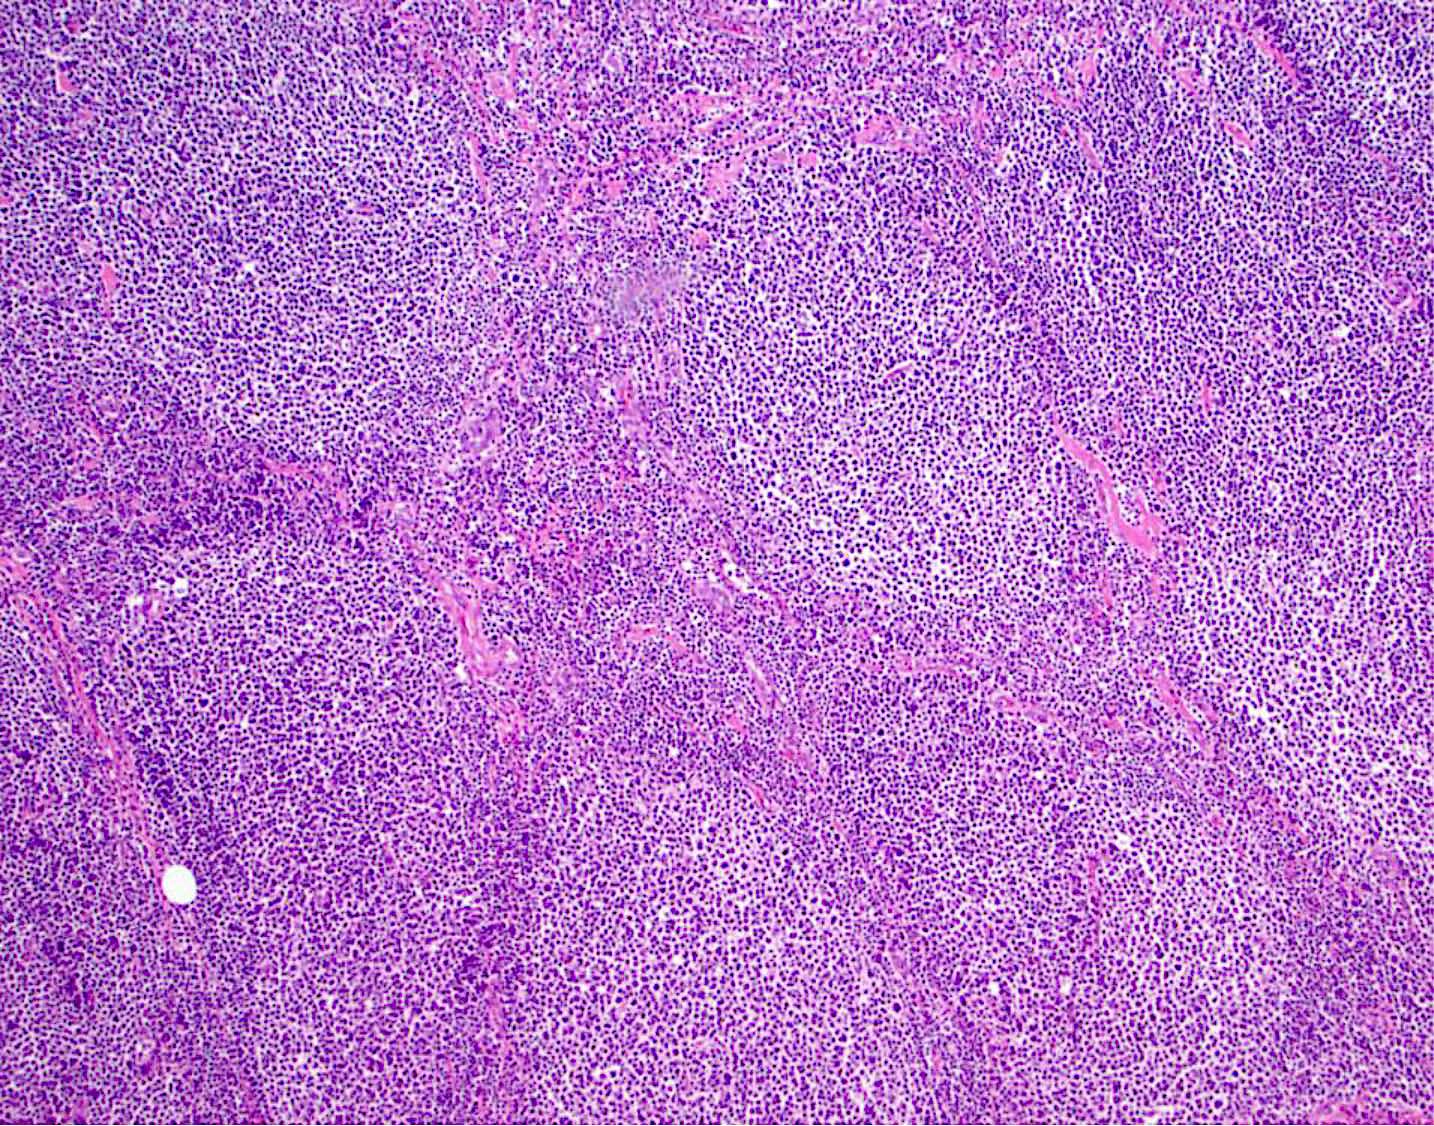

Microscopic (histologic) description

- Lymph node

- Partial or complete effacement of lymph node

- Neoplastic follicles:

- Similarly sized

- Nonpolarized

- Attenuated or absent mantle zones

- Lack tingible body macrophages

- Composed of centrocytes or centroblasts

- Infrequent mitoses (except grade 3)

- With or without sclerosis

- Grading: proportion of centroblasts defines the grade

- Follicular dendritic cell meshworks are absent in diffuse areas

Microscopic (histologic) images